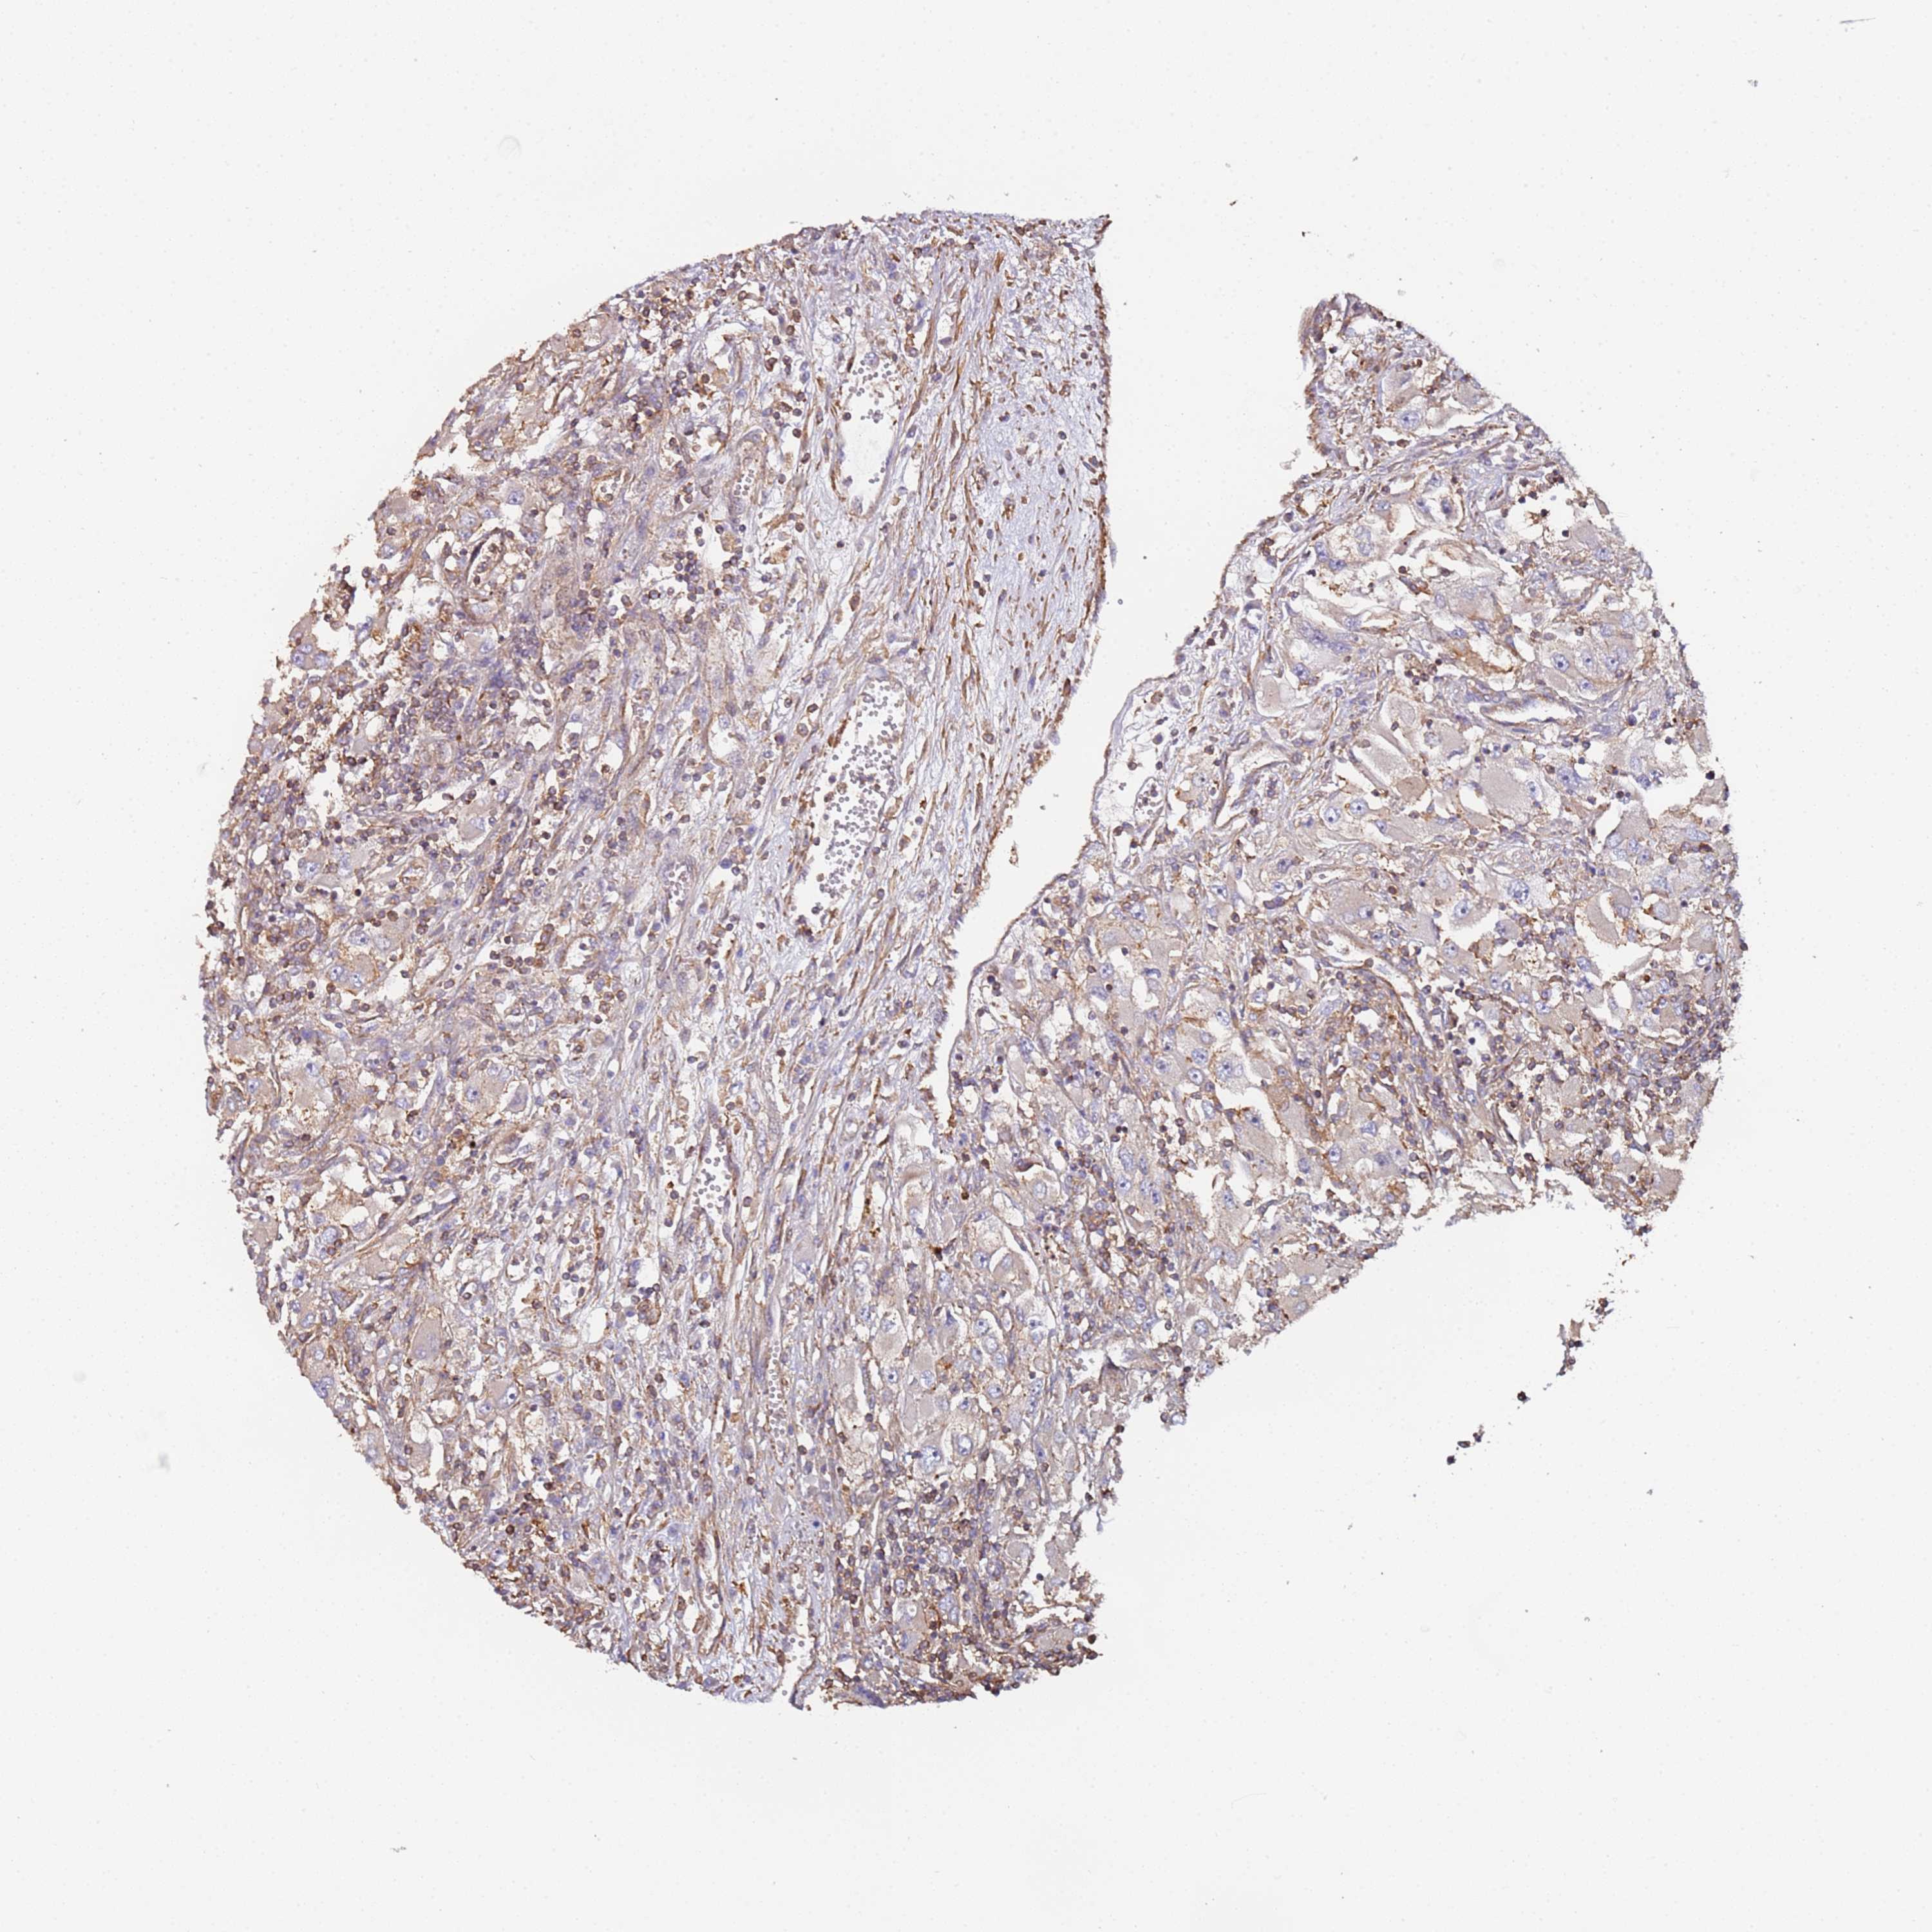

KIDNEY RENAL CLEAR CELL CARCINOMA (VALIDATION) - Interactive survival scatter ploti

The Survival Scatter plot shows the clinical status (i.e. dead or alive) for all individuals in the patient cohort, based on the same data that underlies the corresponding Kaplan-Meier plots. Patients that are alive at last time for follow-up are shown in blue and patients who have died during the study are shown in red.

The x-axis shows the expression levels (FPKM) of the investigated gene in the tumor tissue at the time of diagnosis. The y-axis shows the follow-up time after diagnosis (years). Both axes are complimented with kernel density curves demonstrating the data density over the axes. The top density plot shows the expression levels (FPKM) distribution among dead (red) and alive patients (blue). The right density plot shows the data density of the survived years of dead patients with high and low expression levels respectively, stratified using the cutoff indicated by the vertical dashed line through the Survival Scatter plot. This cutoff is automatically defined based on the FPKM cutoff that minimizes the p-score. The cutoff can be changed by dragging the vertical line or by entering a cutoff value in the square labeled "Current cut-off".

Under the Survival Scatter plot the p-score landscape (black curve; left axis) is shown together with dead median separation (red curve; right axis). Dead median separation is the difference in median mRNA expression between patients who have died with high and low expression, respectively. It is calculated as follows: median FPKM expression of dead patients with high expression - median FPKM expression of dead patients with low expression. This is intended to aid the user in visually exploring custom cutoffs and the associated p-scores and dead median separation.

Individual patient data is displayed and can be filtered by clicking on one or more of the category buttons on the top of the page. Categories describing expression level and patient information include: high, low, alive, dead, female, male and tumor stages. The scale of the x-axis can be toggled between linear and log-scale by clicking on the "x log" button. Mouse-over function shows TCGA ID, patient information and mRNA expression (FPKM) for each patient.

& Survival analysisi

Kaplan-Meier plots summarize results from analysis of correlation between mRNA expression level and patient survival. Patients were divided based on level of expression into one of the two groups "low" (under cut off) or "high" (over cut off). X-axis shows time for survival (years) and y-axis shows the probability of survival, where 1.0 corresponds to 100 percent.

CYP2U1 is not prognostic in Kidney Renal Clear Cell Carcinoma (validation)

Best expression cut offi

Based on the FPKM value of each gene, patients were classified into two groups and association between prognosis (survival) and gene expression (FPKM) was examined. The best expression cut-off refers the FPKM value that yields maximal difference with regard to survival between the two groups at the lowest log-rank P-value. Best expression cut-off was selected based on survival analysis .

When clicking on this number, the vertical dashed line indicating cut-off, the interactive survival plot, and the Kaplan-Meier curve will be adjusted to show results based on the best expression cut-off.

: 5.77

P scorei

Log-rank P value for Kaplan-Meier plot showing results from analysis of correlation between mRNA expression level and patient survival.

N/A

TCGA RNA samplesi

RNA-seq data is reported as average FPKM (number Fragments Per Kilobase of exon per Million reads), generated by the The Cancer Genome Atlas (TCGA) .

Normal distribution across the dataset is visualized with box plots, shown as median and 25th and 75th percentiles. Points are displayed as outliers if they are above or below 1.5 times the interquartile range. FPKM values of the individual samples are presented next to the box plot.

Average pTPM 7.3

Number of samples 100